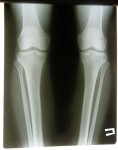

2 месяца с момента снятия аппаратов.

Пациентке разрешена нагрузка без ограничений!